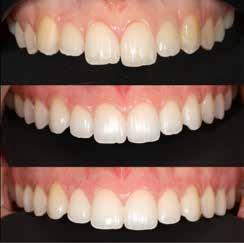

A hiányzó oldalsó kismetszők részárással történő kezelése során a szemfogak és oldalsó fogak meziális mozgatása közben a fogszabályozó orvosnak csiszolással kell a fogak formáját igazítani. Már a kezelés elejétől a szemfog elcsiszolása nem csak az incizális részre kell hogy kiterjedjen, hanem az approximális, palatinális és a vesztibuláris felszín éli negyedére is. Így érhetünk el egy rövidebb klinikai koronát, a vesztibulo-orális méret csökkenését, egy incizális élet, valamint a szemfog megfelelő pozicionálását a kismetsző helyén. A túl széles szemfog megakadályozza a megfelelő interkuszpidáció kialakítását az oldalzónában. A palatinális felszín elcsiszolásával biztosítjuk az interferenciák nélküli metszővezetést, és a megfelelő overjetet a frontfogak enyhe érintkezésével. Ha a szemfogra a későbbiekben esztétikai pótlás készül, a megfelelő approximális elcsiszolás (az esztétikai fogorvossal történő egyeztetés után) biztosítja a zenith kívánatos pozícióját a későbbi felépítéshez. A mezializált kisőrlő palatinális csücskének elcsiszolására csak akkor van szükség, ha ez akadályozza a megfelelő fogérintkezést. Az első kisőrlő mindkét csücske fontos a már a szemfog helyén álló fog esztétikai és funkcionális beállításához.

A szemfog oldalsó kismetsző helyére történő bemozgatása során a fog átalakítása javasolt a két fog eltérő morfológiai adottságai miatt (1. a-b. ábra). A fog kontúrozása, vagy úgynevezett formázása magába foglalja az approximális felszínek elcsiszolását, valamint a többi fogfelszín igazítását a kívánt fogformának megfelelően [1].

Szemfog mezializációt követően történik az approximális felszínek igazítása. Elérjük a megfelelő mezio-disztális szélességet, és a kontaktpont incizális irányba helyeződik át. Ebben a fázisban mindig szükséges egyeztetni az esztétikai pótlást készítő fogorvossal a szükséges szemfogformáról és a későbbi felépítmény pontos helyzetéről. Az esztétikai fogorvosnak kell eldöntenie a meziális és disztális felszínek elcsiszolásának mértékét is.